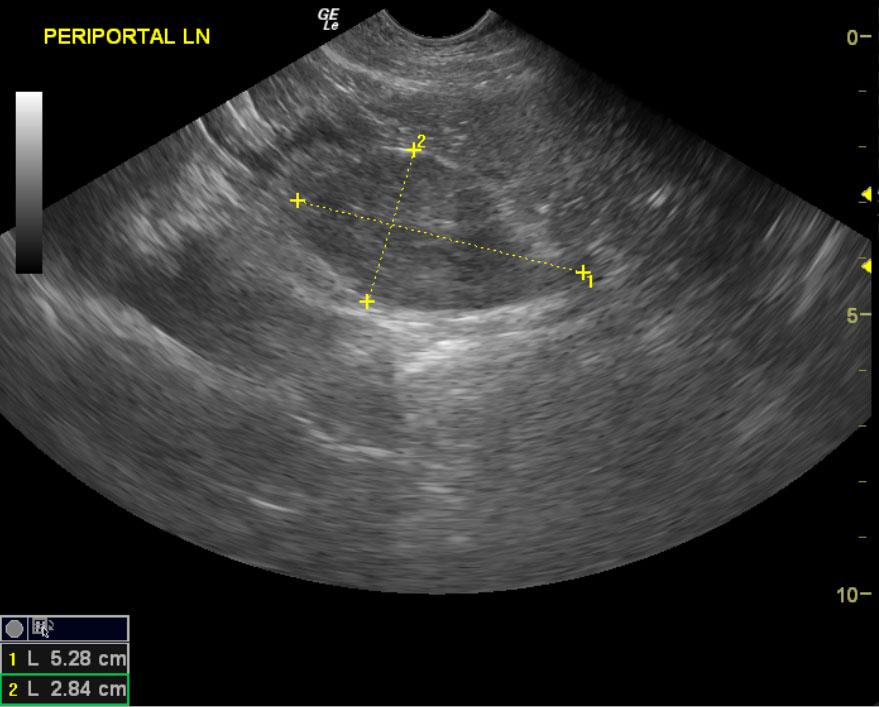

From members.sonopath.com

Lymphoma in a 4 year old FS Labrador Retriever mix dog Members Labrador Retriever Lymphoma Learn more about symptoms, stages, and treatments of canine lymphoma. Enlarged lymph nodes may also occur due to infections or autoimmune diseases, so your veterinarian will perform tests to determine the. Lymphosarcoma is a common cancer of lymphocytes in dogs and can occur in. Learn about the signs of lymphoma in dogs, the stages, treatments, and possible life expectancy of. Labrador Retriever Lymphoma.

Lymphoma in a 4 year old FS Labrador Retriever mix dog Members Labrador Retriever Lymphoma Lymphosarcoma is a common cancer of lymphocytes in dogs and can occur in. Not all dogs with enlarged lymph nodes have lymphoma. Enlarged lymph nodes may also occur due to infections or autoimmune diseases, so your veterinarian will perform tests to determine the. Dog lymphoma is cancer affecting white blood cells. Learn about the signs of lymphoma in dogs, the. Labrador Retriever Lymphoma.

Lymphoma in a 4 year old FS Labrador Retriever mix dog Members Labrador Retriever Lymphoma Learn more about symptoms, stages, and treatments of canine lymphoma. Enlarged lymph nodes may also occur due to infections or autoimmune diseases, so your veterinarian will perform tests to determine the. One of the most common instances of dog cancer is lymphoma. Not all dogs with enlarged lymph nodes have lymphoma. Lymphosarcoma is a common cancer of lymphocytes in dogs. Labrador Retriever Lymphoma.

Lymphoma in a 4 year old FS Labrador Retriever mix dog Members Labrador Retriever Lymphoma One of the most common instances of dog cancer is lymphoma. Learn about the signs of lymphoma in dogs, the stages, treatments, and possible life expectancy of a dog with lymphoma. Lymphosarcoma is a common cancer of lymphocytes in dogs and can occur in. Not all dogs with enlarged lymph nodes have lymphoma. Dog lymphoma is cancer affecting white blood. Labrador Retriever Lymphoma.